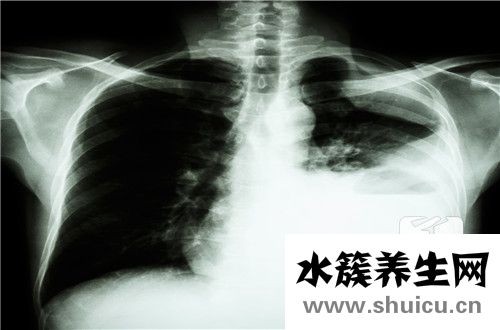

低分化鱗癌可產生于全身好幾個位置,需融合實際分析分辨預后。病理學視角,低分化預兆腫瘤分裂較弱,腫瘤發(fā)作或遷移風險性較高,痊愈實際效果較弱。低分化鱗癌需融合實際腫瘤生長發(fā)育位置開展剖析,如鼻咽部腫瘤,因為其放療化療敏感度不錯,初期可徹底痊愈。但假如鱗癌生長發(fā)育位置不佳,沒法手術治療摘除、部分放化療,或病人本身情況較弱,沒法接納合理抗腫瘤醫(yī)治,則預后較弱。